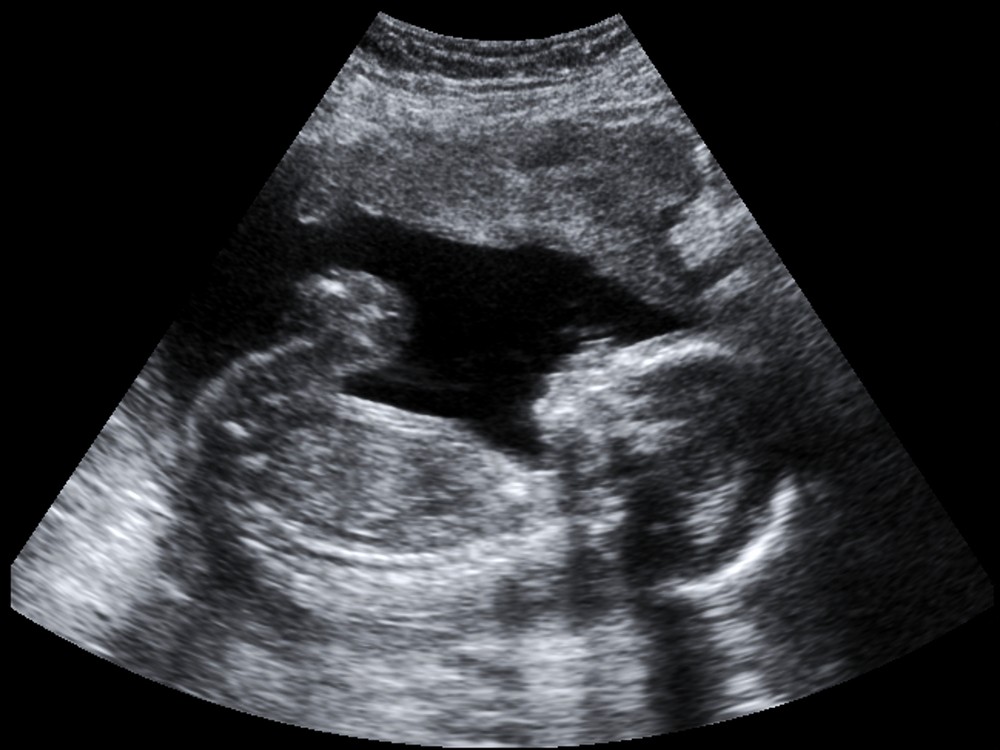

像是很多媽媽討論區會出現的「胎內記憶」,或是讓胎兒聽音樂有助成長等等,都引起很多共鳴,日前就有一名媽媽在社群平台「Dcard」發文說,自己懷孕之後原本覺得是喜事,不過產檢初期結果,似乎是懷上女生,讓老公的阿嬤相當不滿意。

有一位媽媽在dcard發文表示,原本懷孕是好事一樁,家人也都期待孩子的到來,誰知道產檢後發現,肚子裡面的孩子應該是女生,老公的阿嬤得知後,馬上就態度大轉變,除了在生活上刁難,故意在大雨天、大熱天,把她關在門外面,還說根本就是因為她,讓家裡斷了香火,只要看到這名女網友,就一直驅趕去別的地方,還說都是因為懷了女兒,讓自己的中風發作。

直到發現肚子裡面懷的是兒子後,因為家裡鬧得也不愉快,老公就帶著她回娘家待產,沒想到當初還擺臉色的阿嬤,竟然到處哭訴,說曾孫被帶走,讓她實在很無奈,直呼:「就還在我肚子裡面是要怎樣!」不過還好後來也順利生下來了。